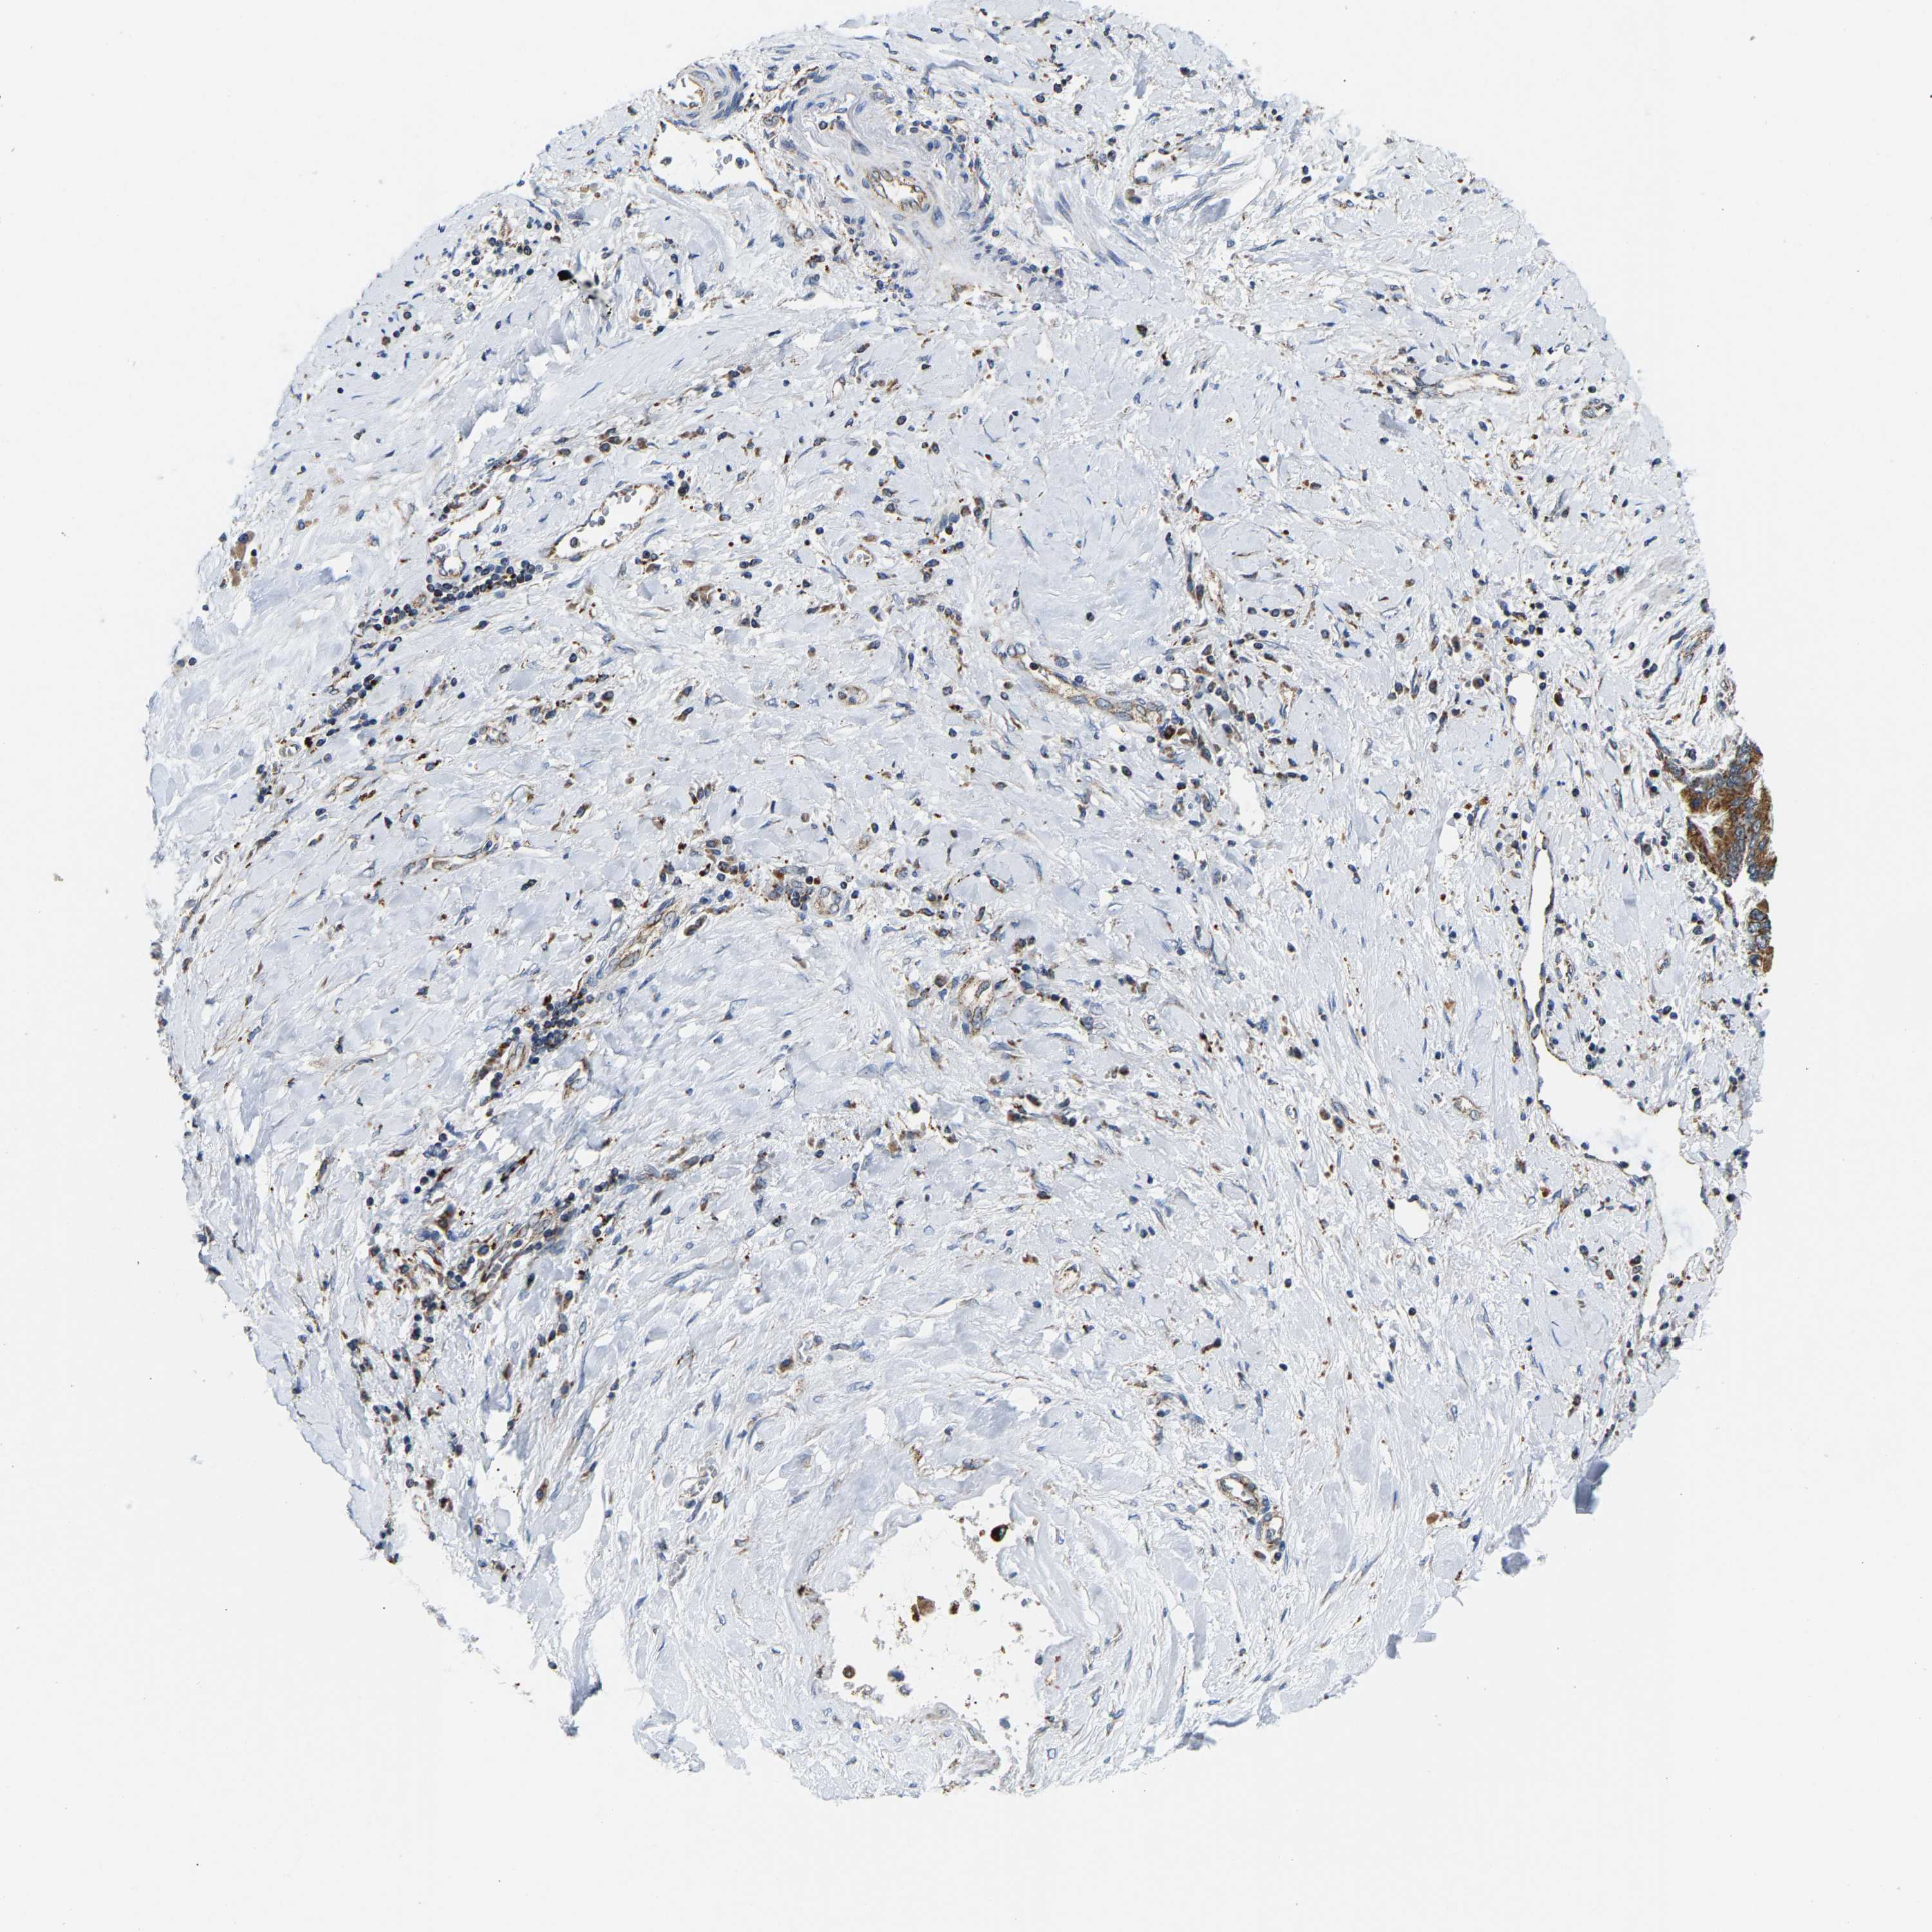

LIVER CANCER - Protein expressioni

A mouse-over function shows sample information and annotation data. Click on an image to view it in a full screen mode. Samples can be filtered based on level of antibody staining by selecting one or several of the following categories: high, medium, low and not detected. The assay and annotation is described here.

Note that samples used for immunohistochemistry by the Human Protein Atlas do not correspond to samples in the TCGA dataset.

Antibody stainingi

Antibody staining in the annotated cell types in the current human tissue is reported as not detected, low, medium, or high, based on conventional immunohistochemistry profiling in selected tissues. This score is based on the combination of the staining intensity and fraction of stained cells.

Each image is clickable and will lead to virtual microscopy that enables deeper exploration of all samples and also displays staining intensity scores, fraction scores and subcellular localization as well as patient and tissue information for each sample.

Antibody HPA020266

Antibody HPA020268

Staining

High

Medium

Low

Not detected

Intensity

Strong

Moderate

Weak

Negative

Quantity

>75%

75%-25%

<25%

None

Location

Nuclear

Cytoplasmic/membranous

Cytoplasmic/membranous,nuclear

Cholangiocarcinoma

Carcinoma, Hepatocellular, NOS